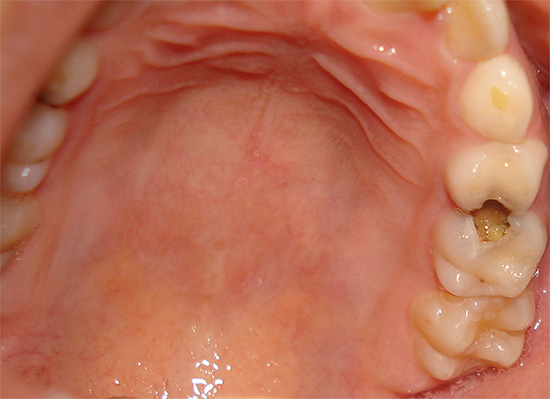

- Não há pontos e traços pretos (os últimos são característicos de cárie de fissura).

Se houver um orifício no esmalte (cavidade), definitivamente não será possível curar um dente sem obtê-lo. Em muitos casos, essas lesões de cárie que só podem ser tratadas por um dentista se apresentam como manchas marrons ou pretas distintas.

Isso é especialmente verdadeiro para fissuras, onde esses pontos às vezes podem ser muito pequenos e não se incomodam com nada, e é por isso que muitos não os percebem como um problema sério. Enquanto isso, a área da lesão sob essa mancha já pode penetrar profundamente na dentina.

Devido ao pequeno tamanho das áreas escuras na área da fissura, muitos acreditam que esses pontos podem simplesmente ser clareados ou lixados em casa, e a cárie dentária como se isso fosse curado. De fato, essa mancha é apenas um sinal de que a cárie não pode ser curada sem preenchimento.